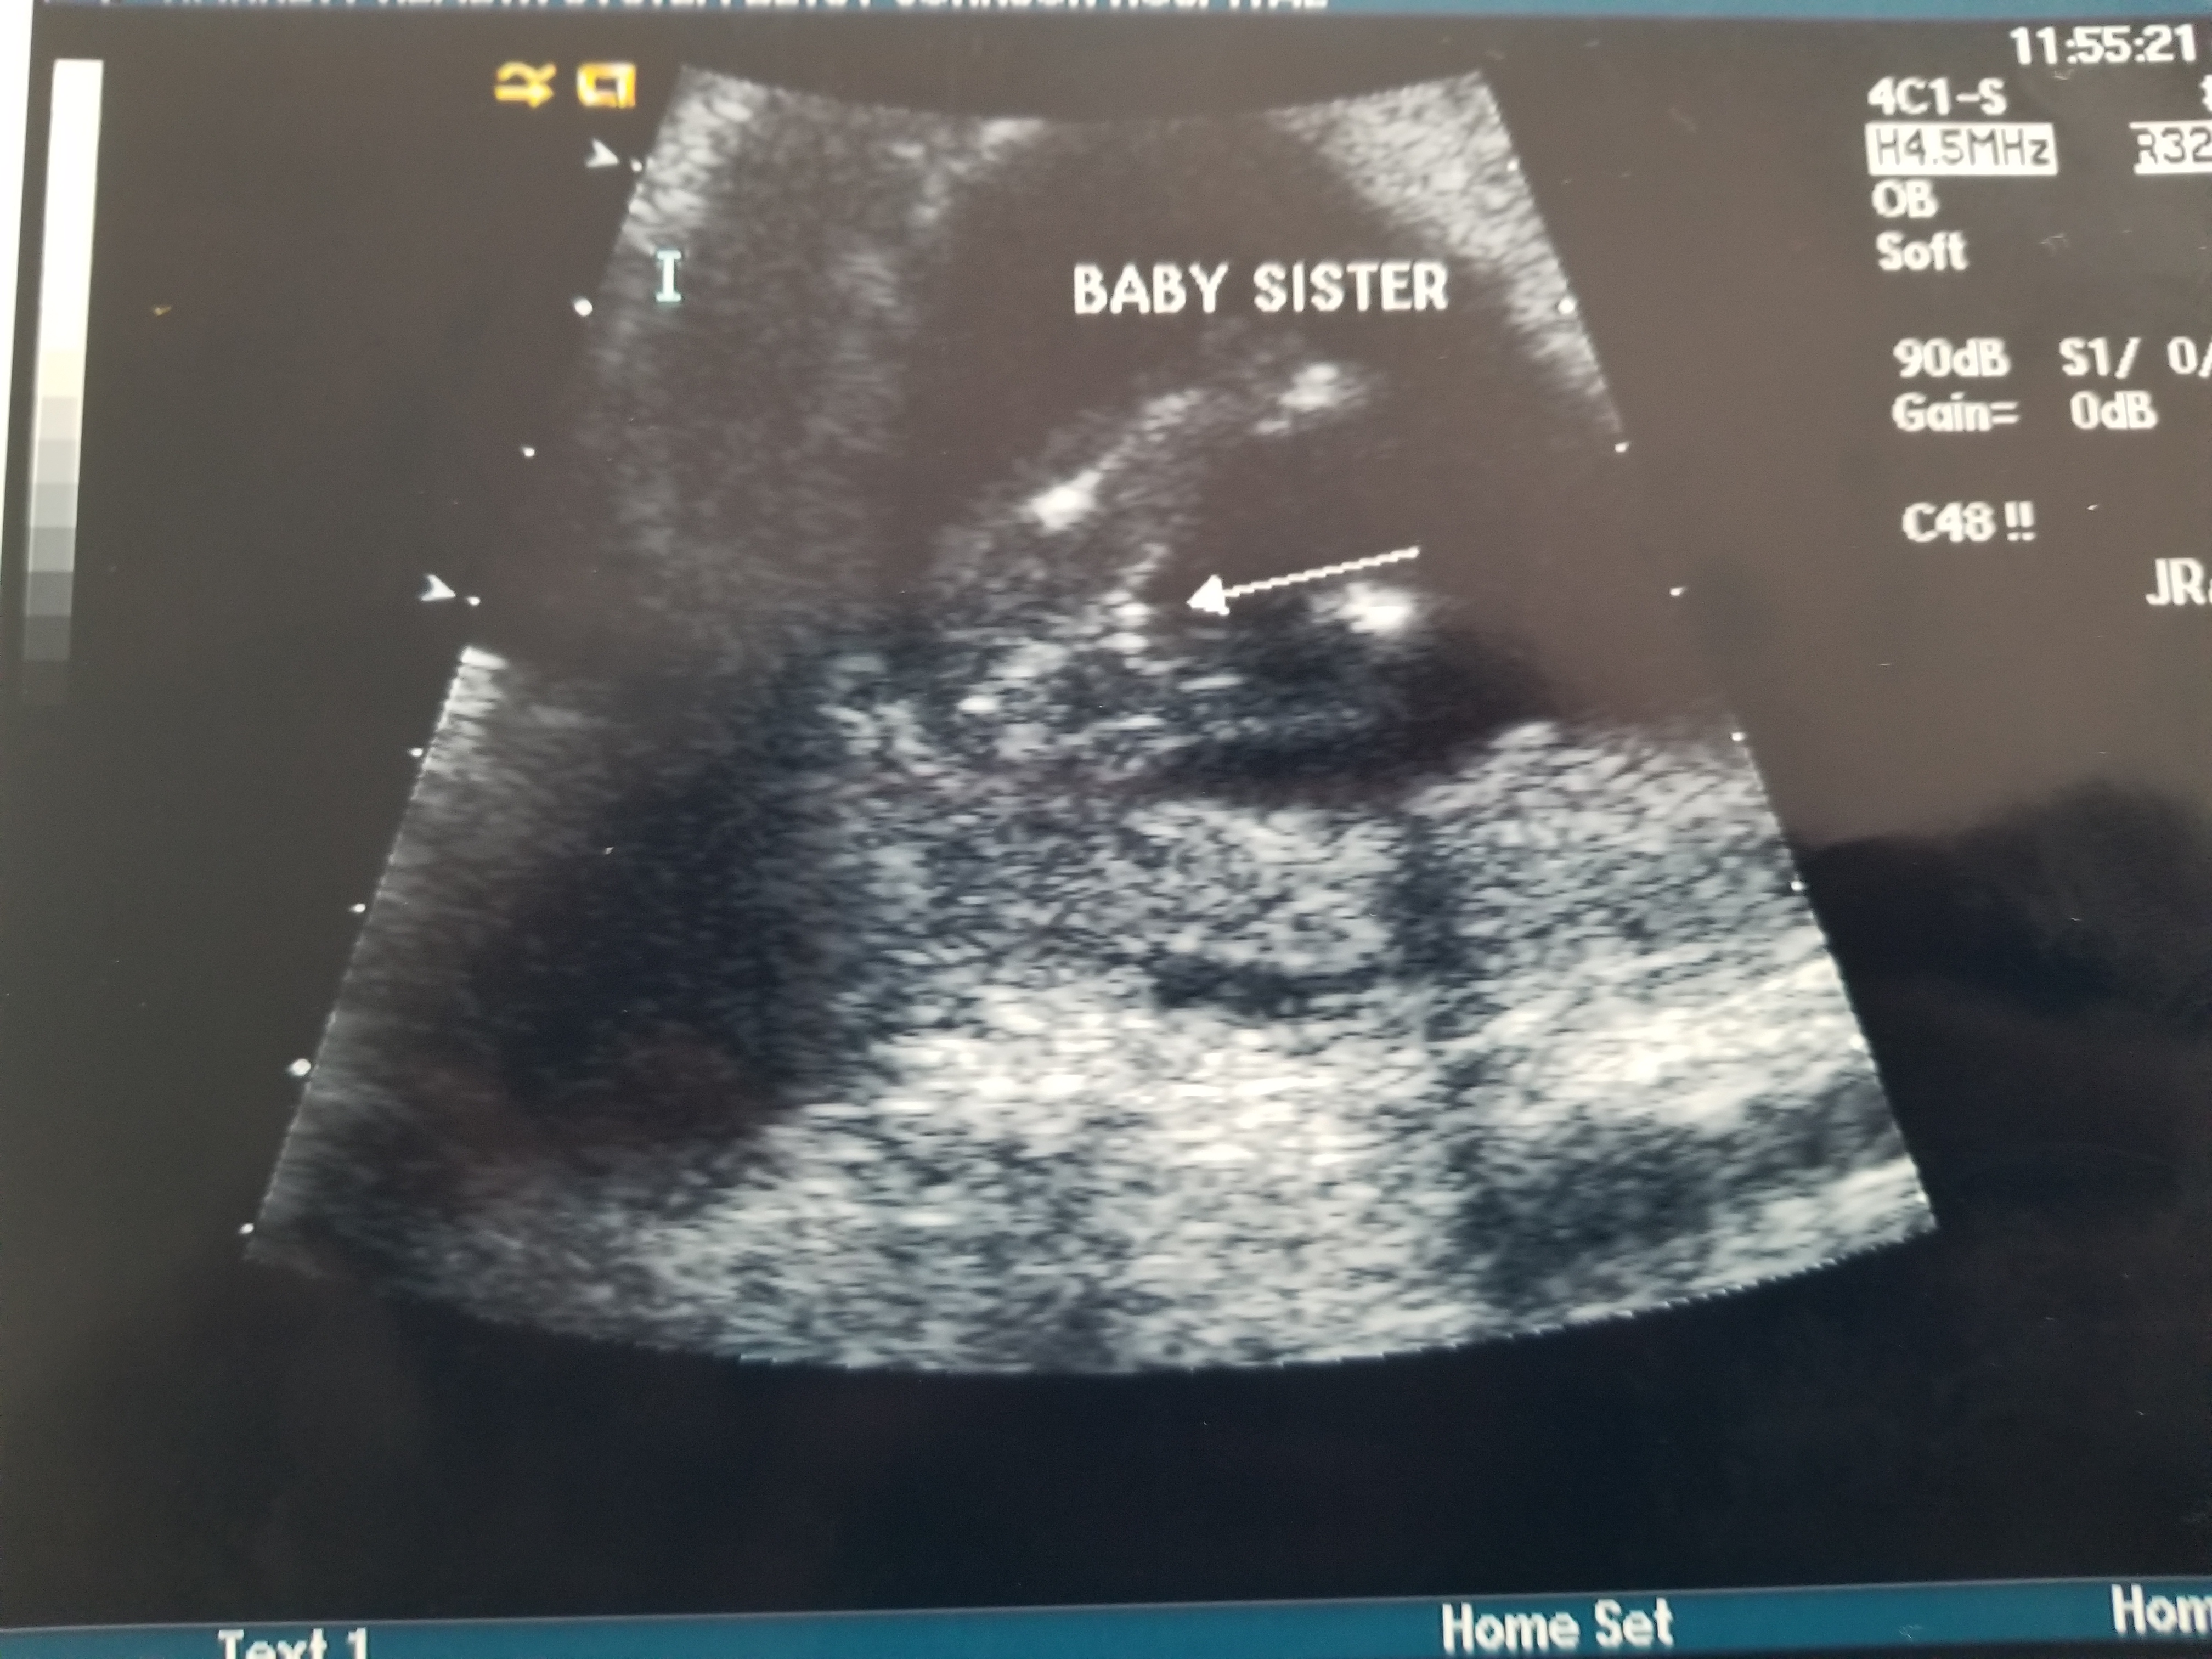

Hi everyone! I'm 15 weeks today and my doctor sent me to the hospital to have a scan due to some bleeding. The ultrasound tech said she was able to tell the sex. Has anyone else ever found out this early? Does this look like a girl to anyone else? I have 3 boys so I really hope this is my girl this time. I included the pic in this post.Attachment 37067

Is this really my little girl?